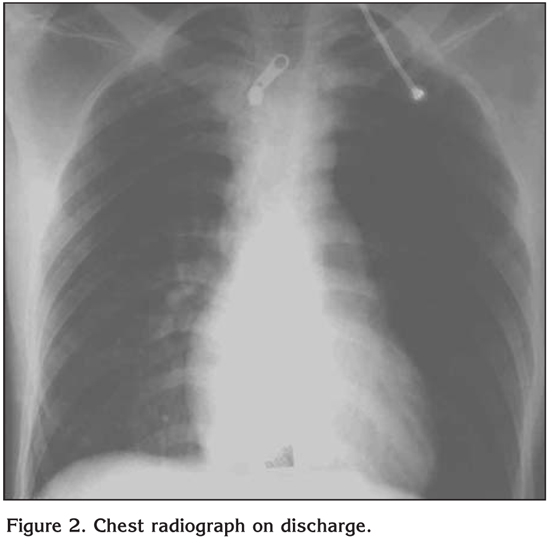

A 23-year old man was admitted to our respiratory intensive care unit with short of breath, cyanosis and agitation which was developed acutely after varicocele operation under epidural anesthesia lasted for one hour. Bupivacain, fentanyl, remifentadyl and midazolam were used for epidural anesthesia. There was no blood transfusions history of patient. On admission his temperature was 38?C, heart rate 117 was beats/minute, respiratory rate was 48 breaths/minute and blood pressure was 110/70 mmHg. He was tachypneic, agitated and cyanotic. Bilateral ralles were heart during auscultation and tachycardia was present. The rest of the physical examination was unremarkable. His blood count and biochemical analysis were normal. Oxygen saturation was 81% while breathing oxygen at FiO2 of 0.5. Arterial blood gas analysis showed hypoxemia with respiratory alkalosis with a PaO2/FiO2 score of 100. A chest radiograph demonstrated bilateral alveolar opacities consistent with ARDS (Figure 1). An electrocardiogram showed sinus tachycardia. Bedside echocardiography was performed which revealed no evidence of global hypokinesia, all the chambers were normal, left ventricular ejection fraction was 65%. The right atrium and right ventricle were normal with minimal tricuspid regurgitation. A diagnosis of ARDS was made and the patient was initiated on NIMV (BiPAP, Respironics, Inc, Murrysville, PA, ABD) with an expiratory/inspiratory positive airway pressure of 4/10 cmH2O with a FiO2 of 0.5. Over the next hour, there was partially improvement in oxygen saturation, respiratory rate and arterial blood gas parameters. PaO2/FiO2 score was calculated 116. He was continued with an expiratory/inspiratory positive airway pressure of 5/12 cmH2O with a FiO2 of 0.7. After 48 hours of continuous ventilation (with short breaks for daily activities), there was a significant improvement in the PaO2/FiO2 score and radiographic findings (Figure 2). PaO2/FiO2 score was calculated 213. He was gradually weaned off the NIMV and discharged after a total hospital stay of four days. Nonspecific antibiotic was continued for four days. At a one-week follow up, he was asymptomatic and his chest radiography was normal.

Figure 2